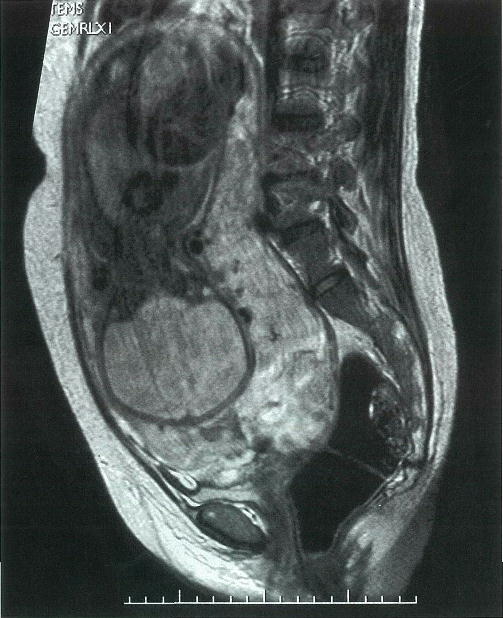

第75話 真性包茎手術+癒着剥離 難易度MAX編 画像あり 真性包茎+ ・・・・・これでは性交渉がままならないとある日、意を決して包皮を無理やり剥いたところ、亀頭と包皮がくっついていた。 ・・・・・これが真性包茎+癒着の状態です。 見た目は真性 関節リウマチや変形性膝関節症の末期では、「膝関節の関節の変形」と「痛み」を伴うため、それらの改善のために人工膝関節全置換術(TKA:Total Knee Arthroplasty))を施行することがあります。 ここでは、TKA術後の"膝関節の屈曲制限"に対して「どうアプローチをしていけば良い画像診断 39巻7号 (19年5月) 癒着胎盤は分娩時に致命的な大量出血を来す,産科的に重要な疾患である.集学的かつ計画的な帝王切開により術中出血量の減少が期待できるため,分娩前に正しく診断することが重要である.超音波検査に続いてMRIが重要